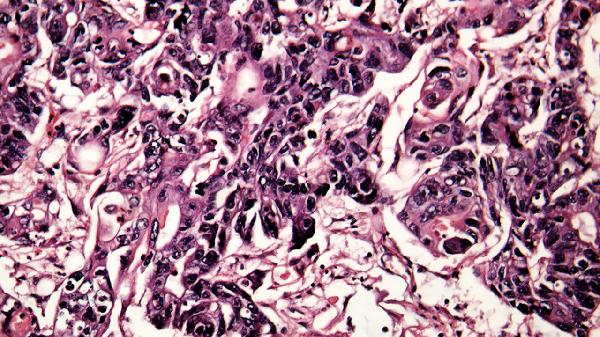

部分病毒感染可直接侵犯脑组织引发脑炎,例如单纯疱疹病毒、狂犬病毒等。病毒侵入脑实质后会导致神经元损伤,患者可能出现意识模糊、定向力障碍、幻觉或攻击行为等精神症状。流行性乙型脑炎患者急性期可能出现躁狂、谵妄等表现,重症者可发展为昏迷。某些呼吸道病毒如流感病毒引发的全身炎症反应综合征,也可能通过血脑屏障影响神经递质平衡,导致暂时性精神行为异常。

特殊情况下,病毒感染可能诱发自身免疫性脑炎,例如抗NMDAR脑炎。这类疾病初期常表现为精神症状如妄想、情绪失控,易被误诊为精神疾病。此外,艾滋病晚期因HIV病毒破坏免疫系统,可能引发艾滋病痴呆综合征,患者会出现进行性认知功能下降和行为异常。长期新冠病毒感染后也有报告出现脑雾、情绪障碍等神经系统后遗症。